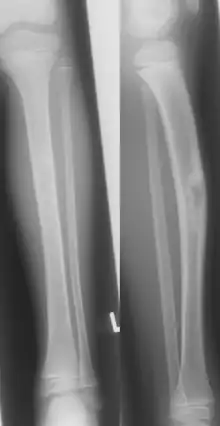

Jaffe-Campanacci-Syndrome, boy 7 Y, tibial bowing and cortical/subcortial mixed sclerosis